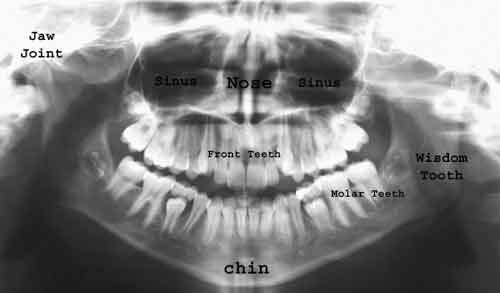

Ortopantomografia

Ortopantomografia PRINCIPII TEHNICE n Miscarea de rotatie tub-caseta n Miscarea de translatie a casetei in port-caseta Imagini fantoma n Citeste tot ... 453 cuvinte

Dimensiune mica

+ cu imagini |